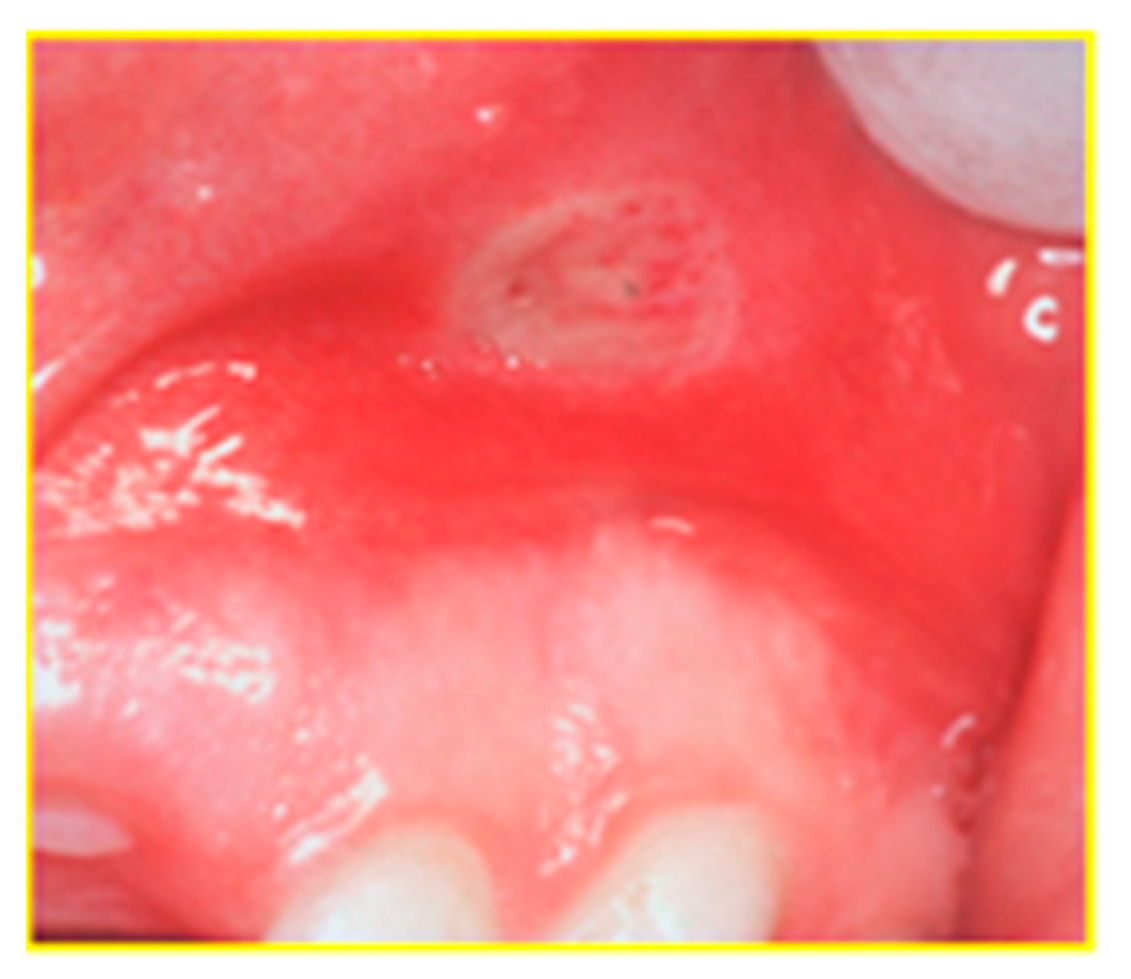

| Aphthous ulcerations | X | X |

| 2 | Elahi et al. [13] | CC; Iran | 100 (54/46); 39 ± 25,6 yr. Cr = 50 (26/24); 40 ± 20 yr | UC = 50 (28/22); 38 ± 16 yr | Oral ullerations = 20 (p = 0.028); tongue coating = 14 (p = 0.012); dry mouth = 30 (p = 0.023); halitosis = 34 (p = 0.001); acidic taste = 20 (p = 0.008), taste changes = 20 (p 0.001) | NN | NN | NO | NN |

| 10 | Koutsochristou et al. [9] | CC; Greece | 110 (50/60); 12.26 ± 5.22 yr Cr = 55 (25/30); 12.21 ± 3,96 yr | CD = 36 (18/18); UC = 19 (7/12); 13 of 55 patients had oral lesions (23%) | Aphthae = 8, aphthae with swelling of gums or ulcers or candidiasis = 5 | DMFT IBD = 5.81 (p < 0.001) Cr = 2.04 dmft IBD = 2.95 (p < 0.001) Cr = 0.91 | CPITN index: IBD: score 0 = 0 (0%) score 1 = 20 (36%) score 2 = 30 (54%) score 3 = 5 (9%) Cr: score 0 = 22 (40%) score 1 = 25 (45%) score 2 = 8 (14%) score 3 = 0 (0%) | aminosalicylates, corticosteroids, anti-TNF, or immuno-modulators | NN |

| 11 | Laranjeira et al. [15] | CC; Portugal | 171 (85/86); 45.5 ± 16.9 yr. Cr = 58 (28/30); 47.4 ± 16.3 yr | CD = 65 (32/33); 41.1 ± 15.2 yr. UC = 48 (25/23); 49.2 ± 18.4 yr | Aphtous ulcers = 1 0 (8.80%), (p = 0.159 so NS); gingival swelling = 1 (0.90%), angular cheilitis = 1 (0.90%), halitosis (p = 0.038). | NN | NN | Corticosteroids,salicylate, immunosuppressants, | Non smokers Cr = 52 CD =52; UC = 42 Smokers Cr = 6 CD = 13; UC = 6 |

| 12 | Mohan Kumar et al. [16] | CC; India | 30 (16/14) | UC = 15 (8/7) | Aphtous ulcerations = 10 lichen planus = 3 dry mouth = 11 PSV = 1, coated tongue = 4 NS dysgeusia = 5, halitosis = 12 | NN | Periodontal status NS: Periodontal index UC = 1. Cr = 1.4 gingival index UC = 1.2 Cr = 1.3 loss of attachment (mm) = UC 0.4; Cr = 0.2 | Sulfapyridine; sulfasalazine | NN |

| 13 | Oviedo et al. [19] | T; Chile | 30 (9/21); 40 yr | CD = 7 (2/5) UC = 23 (7/16) | 11 patients (37%): Oral ulcerations = 1 Apthae = 4, angular ulcer = 1, macrocheilia of the lip, corrugated mucosa | NN | NN | NN | NN |

| 14 | Rikardsson et al. [17] | CC; Sweden | 2346 (32.5%/67.5%); 49.6 ± 20, 60 Cr = 748 (33%/67%); 49.5 yr ± 13.8 yr | CD = 1598 (32%/68%); 49.7 ± 15.3 yr | Oral ulcers = 32% (p < 0.001), halitosis = 23% (p < 0-001) mouth dryness = 38% (p < 0.001) toothaches = 21% (p < 0.001) mucosal lesions = 31% (p < 0.001) | Carious lesions = 41% (p < 0.001) | bleeding from gingiva = 41% (p < 0.001) periodontitis = 7% (p < 0.028) | NN | Current smokers CD = 23% Cr = 19% (p < 0.018) former smokers CD = 19% Cr = 15% (p < 0.070) |

| 15 | Szymanska et al. [8] | CC; Sweeden | 225 (102/123); 47.1 ± 24.08 yr Cr = 75 (29/46); 48.6 ± 13.4 yr | CD with RS = 71 (33/38); 50.7 ± 13.9 yr CD without RS = 79 (40/39); 42 ± 14.4 yr | Dry mouth (p = 0.001): 11% in Cr,29% in CD with RS and 38% in CD with NRS Bad breath (p = 0.008):12% in Cr, 21% in CD with RS and 33% in CD with NRS Ulcers (NS): 23% in Cr, 23% in RS and 27% in CD with NRS | Cr = 13.1 CD with RS = 15,5. CD with NRS = 11.2 | NN | NN | Cr = 5 CD with RS = 17 CD with NRS = 15 Former smokers Cr = 33 CD with RS = 25 CD with NRS = 30 |

| 16 | Zervou et al. [18] | CC; Greece | 74; 41,5 ± 20 yr. Cr = 47;43 ± 12 yr | CD = 15 UC = 15 | Ulcers = 3 (2 CD,13% (p = 0.011); 1 UC,7%, (p = 0.07)) cobblestoning = 3 CD,20%, (p = 0.002) polypoids tags = 3 CD,20%, (p = 0.002) lip swelling = 4 (3 CD,20%, (p = 0.002); 1 UC, 7%, (p = 0.07)) buccal swelling = 1 CD,7%, (p = 0.07) aphthous ulcers = 1 UC,7%, (p = 0.07) angular cheilitis = 9 (5 CD, 33% (p = 0.000); 4 UC,27%, (p < 0.0001)) Hairy tongue = 3 (2 CD, 13%, (p = 0.011); 1 UC (p = 0.07)) buccal trauma = 9 (6 CD, 40%, (p = 0.000); 3 UC, 20% (p < 0.00019)) | NN | Periodontitis=2 CD 13%, (p = 0.011) Gingivitis = 4 (3 CD, 20%, (p = 0.002); 1 UC, 7%, (p = 0.07)) Gingival bleeding = 4 CD 27% (p < 0.0001) | Mesalazine, aziathioprine | NN |

| 17 | Zippi et al. [3] | R; Italy | 811 (437/374); 32.5 ± 18,9 EIMs = 329 (155/174) (210 UC;119 CD) | CD = 216 (131/85); 31,9 ± 13,1 yr. UC = 595 (306/289); 33,1 ± 13,7 yr | 6 cases of aphtous stomatitis, 3 CD e 3 UC (1.4% CD e 0.5% UC) | NN | NN | NN | CD Smoker = 98. Non-smoker = 101 Ex smokers = 17. UC Smokers = 140. Ex smokers = 131. Non smokers = 324 |